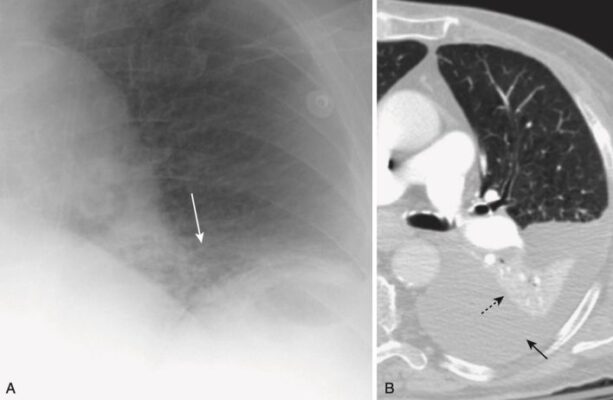

Xẹp phổi tròn (Round atelectasis)

- Hình thức xẹp phổi này thường thấy ở ngoại vi đáy phổi và do sự kết hợp của bệnh màng phổi trước đó (chẳng hạn như tiếp xúc với amiăng hoặc lao) và gây tràn dịch màng phổi tạo ra xẹp phổi cho chèn ép liền kề.

- Khi tràn dịch màng phổi rút đi, bệnh lý màng phổi nền dẫn đến một phần của phổi xẹp bị “kẹt”. Điều này tạo ra một tổn thương dạng khối có thể bị nhầm lẫn với một khối u.

- Trên chụp cắt lớp vi tính (CT) ngực, các dấu hiệu mạch máu phế quản đặc trưng dẫn từ xẹp phổi tròn quay trở lại rốn phổi, tạo ra hình dạng đuôi sao chổi (comet-tail appearance) (Hình 10).